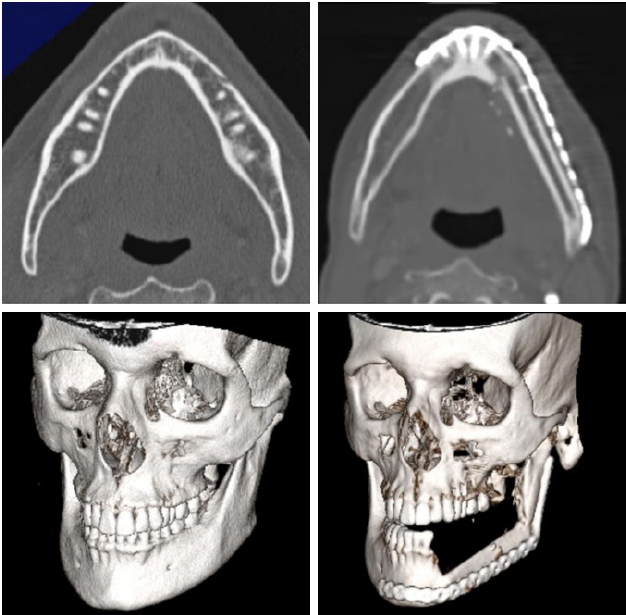

Because of the complex pathway of the vascular pedicle due to the insetting, intraoperative ICG imaging was performed to check the blood supply and the venous drainage after the anastomosis [Figure 6]. The postoperative course was uneventful, and the computed tomography performed at six months confirmed a complete integration of the bone transfer [Figure 7].

Figure 6. Intraoperative picture of the final insetting after mandible reconstruction, where two skin paddles were used to fill the dead space and reconstruct the base of the left part of the tongue (top left, top right); appearance of the vascular supply (bottom left); and ICG proof proper arterial flow and venous drainage (bottom right).